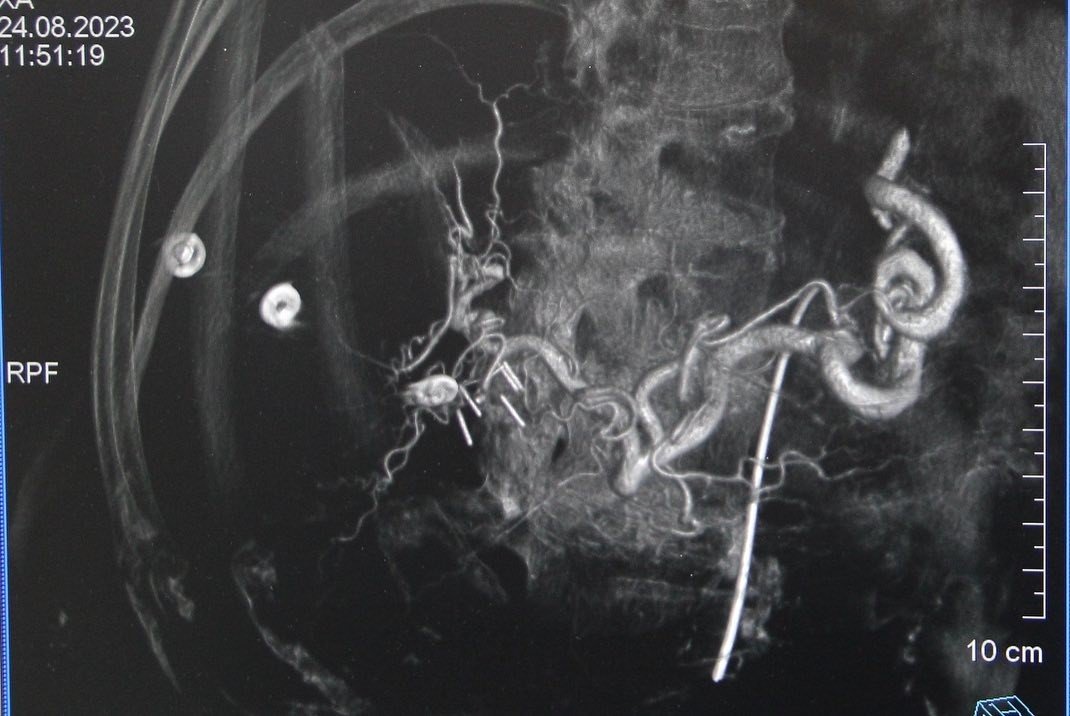

Kütahya Evliya Çelebi Eğitim ve Araştırma Hastanesi Girişimsel Radyoloji Hekimleri Prof. Dr. Mehmet Korkmaz ve Doç. Dr. Furkan Ertürk Urfalı tarafından, Kütahya'da ilk defa karaciğer tümörü olan üç hastaya Transarteriyel Radyoembolizasyon (TARE) işlemi gerçekleştirildi. Başarılı işlem sonrası Transarteriyel Radyoembolizasyon (TARE) hakkında bilgi veren Prof. Dr. Mehmet Korkmaz, "Transarteriyel Radyoembolizasyon, karaciğer kanserlerini ve başka organ kanserlerinin karaciğere metastazlarını tedavi etmek için kullanılan bir tedavi yöntemidir. İçinde radyoaktif madde bulunan çok küçük boyuttaki kürelerin (mikroküre) direkt olarak kanser dokusu içine, kanser damarları yoluyla verilmesidir. Tümör ve metastazlarına yol açan hücrenin bulunduğu alana Nükleer Tıp uzmanlarımız tarafından hesaplanan dozlarla, radyoaktif madde içeren küçük küreciklerin (mikroküreler) enjekte edilmesidir. Radyoaktif madde olan itriyum-90 (Y90) mikroküreler, sağlıklı dokular korunarak, tam olarak tümör üzerine radyasyon uygulayarak etki ederler. Bu sayede çevre dokular zarar görmez. TARE tedavisi ile, karaciğerdeki tümörü küçülterek cerrahi tedaviye uygun hale gelmesini sağlar. Kanserli hücreleri öldürerek hastanın organ nakli için zaman kazanmasını sağlarken, organ nakli için başlangıçta uygun olmayan tümörü küçülterek nakil için imkan sağlar" dedi.

Prof. Dr. Korkmaz, "TARE tedavisinde mikroküreler bir kan damarından geçer ve karaciğer tümörüne direkt ulaşır. Bu sayede radyoaktif madde, diğer radyasyon tedavilerinde olduğu gibi, kanser hücrelerine ulaşmak için vücudun sağlıklı kısımlarından geçmez. Doç. Dr. Furkan Ertürk Urfalı hocamız ve Nükleer Tıp Uzmanımız Dr. Elif Neslihan Akdemir'in destekleriyle birlikte hastanemizde ilk defa üç hastamıza, işlemi başarıyla gerçekleştirmiş bulunmaktayız. Bu işlemlerin yapılmasında emeği geçen ekibime ve bize bu imkanı sağlayan KSBÜ Rektörü Prof. Dr. Ahmet Tekin, İl Sağlık Müdürü Dr. Öğr. Üyesi Sertaş Erarslan ve Başhekim Dr. Öğr. Üyesi Serkan Telli'ye teşekkür ediyorum " dedi.